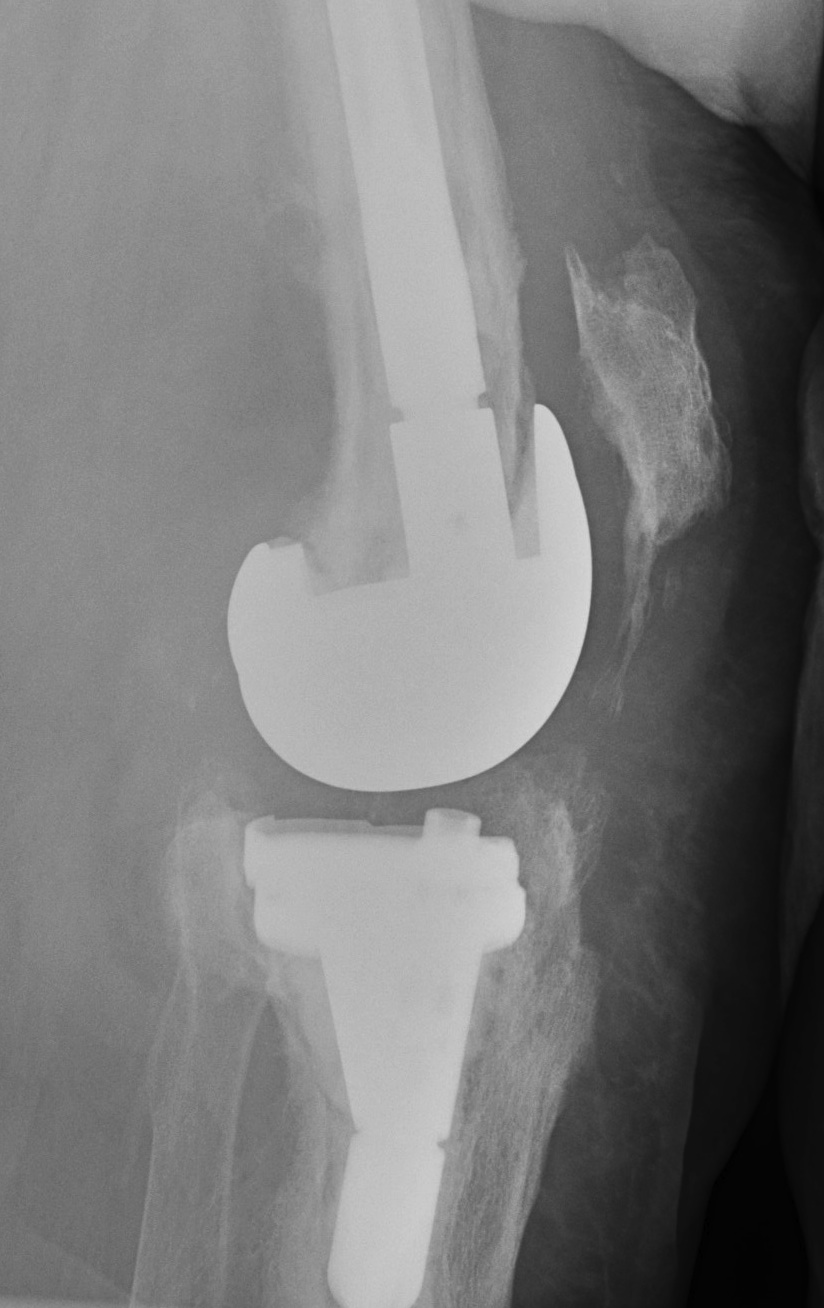

Insert Intermediate implants

A. Block of antibiotic impregnated cement

Good at eradicating infection as high antibiotic load

- painful / poor ROM

- need to be kept in splint

- worsens bone loss

C. Femur and tibia made of antibitoic PMMA

D. Femoral implant from antibiotic cement mould / all poly tibia

Technique

- palacos cement (tobramycin) + 3G vancomycin per bag

- make femoral component from various size moulds

- cement in appropriate size all poly tibia with cement +++

- create a balanced knee

- patients are able to fully weight bear and ROM

- no rush to second stage